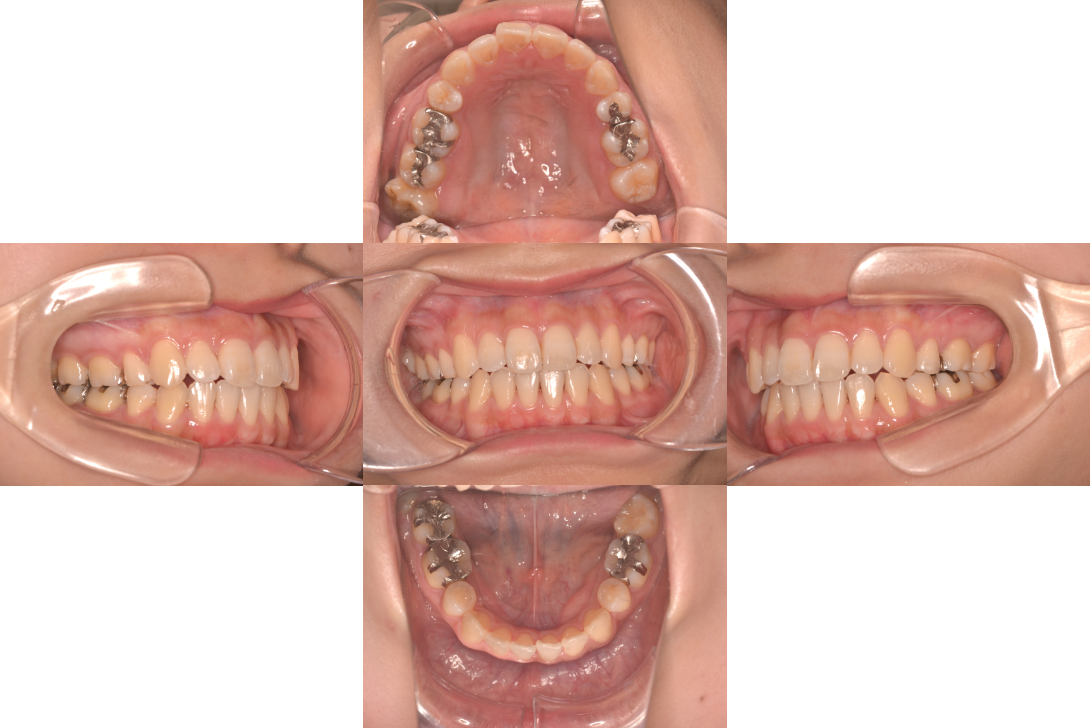

開咬(オープンバイト)を抜歯とDBSで改善した症例

※DBSとはダイレクトボンディングシステムと呼ばれており、ブラケットにワイヤーを通して歯を動かしていく矯正治療です。

患者情報

17歳女性

主訴

ガタガタの歯並びを直したい

行った治療内容

上下顎両側4番抜歯、DBS

治療のリスク

歯肉退縮、歯根吸収

治療期間

動的治療期間4年3か月 (来院がとびとびだった)

※ クリックして拡大することができます。